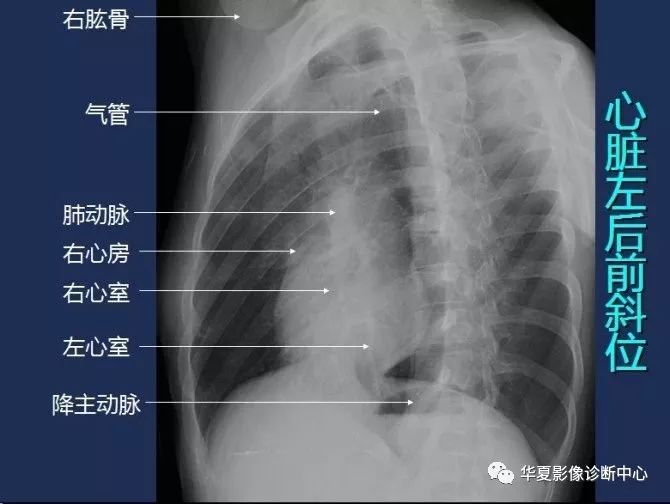

心脏左后前斜位